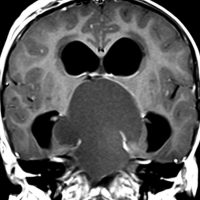

この子の症状は頭痛だけ。両親はなぜ気づかなかったのかと疑問を持ちますが,巨大になるまで症状が出ないこともあるのです。左のCTで腫瘍の周囲にバラバラと白い点状の石灰化があるので診断できます。左の視床下部から発生したクラニオでした。開頭手術しますが超高難易度です,怖いです (┯_┯) 複数回開頭手術になりましたが結果的に全摘出できています (by Dr 山本哲哉)。